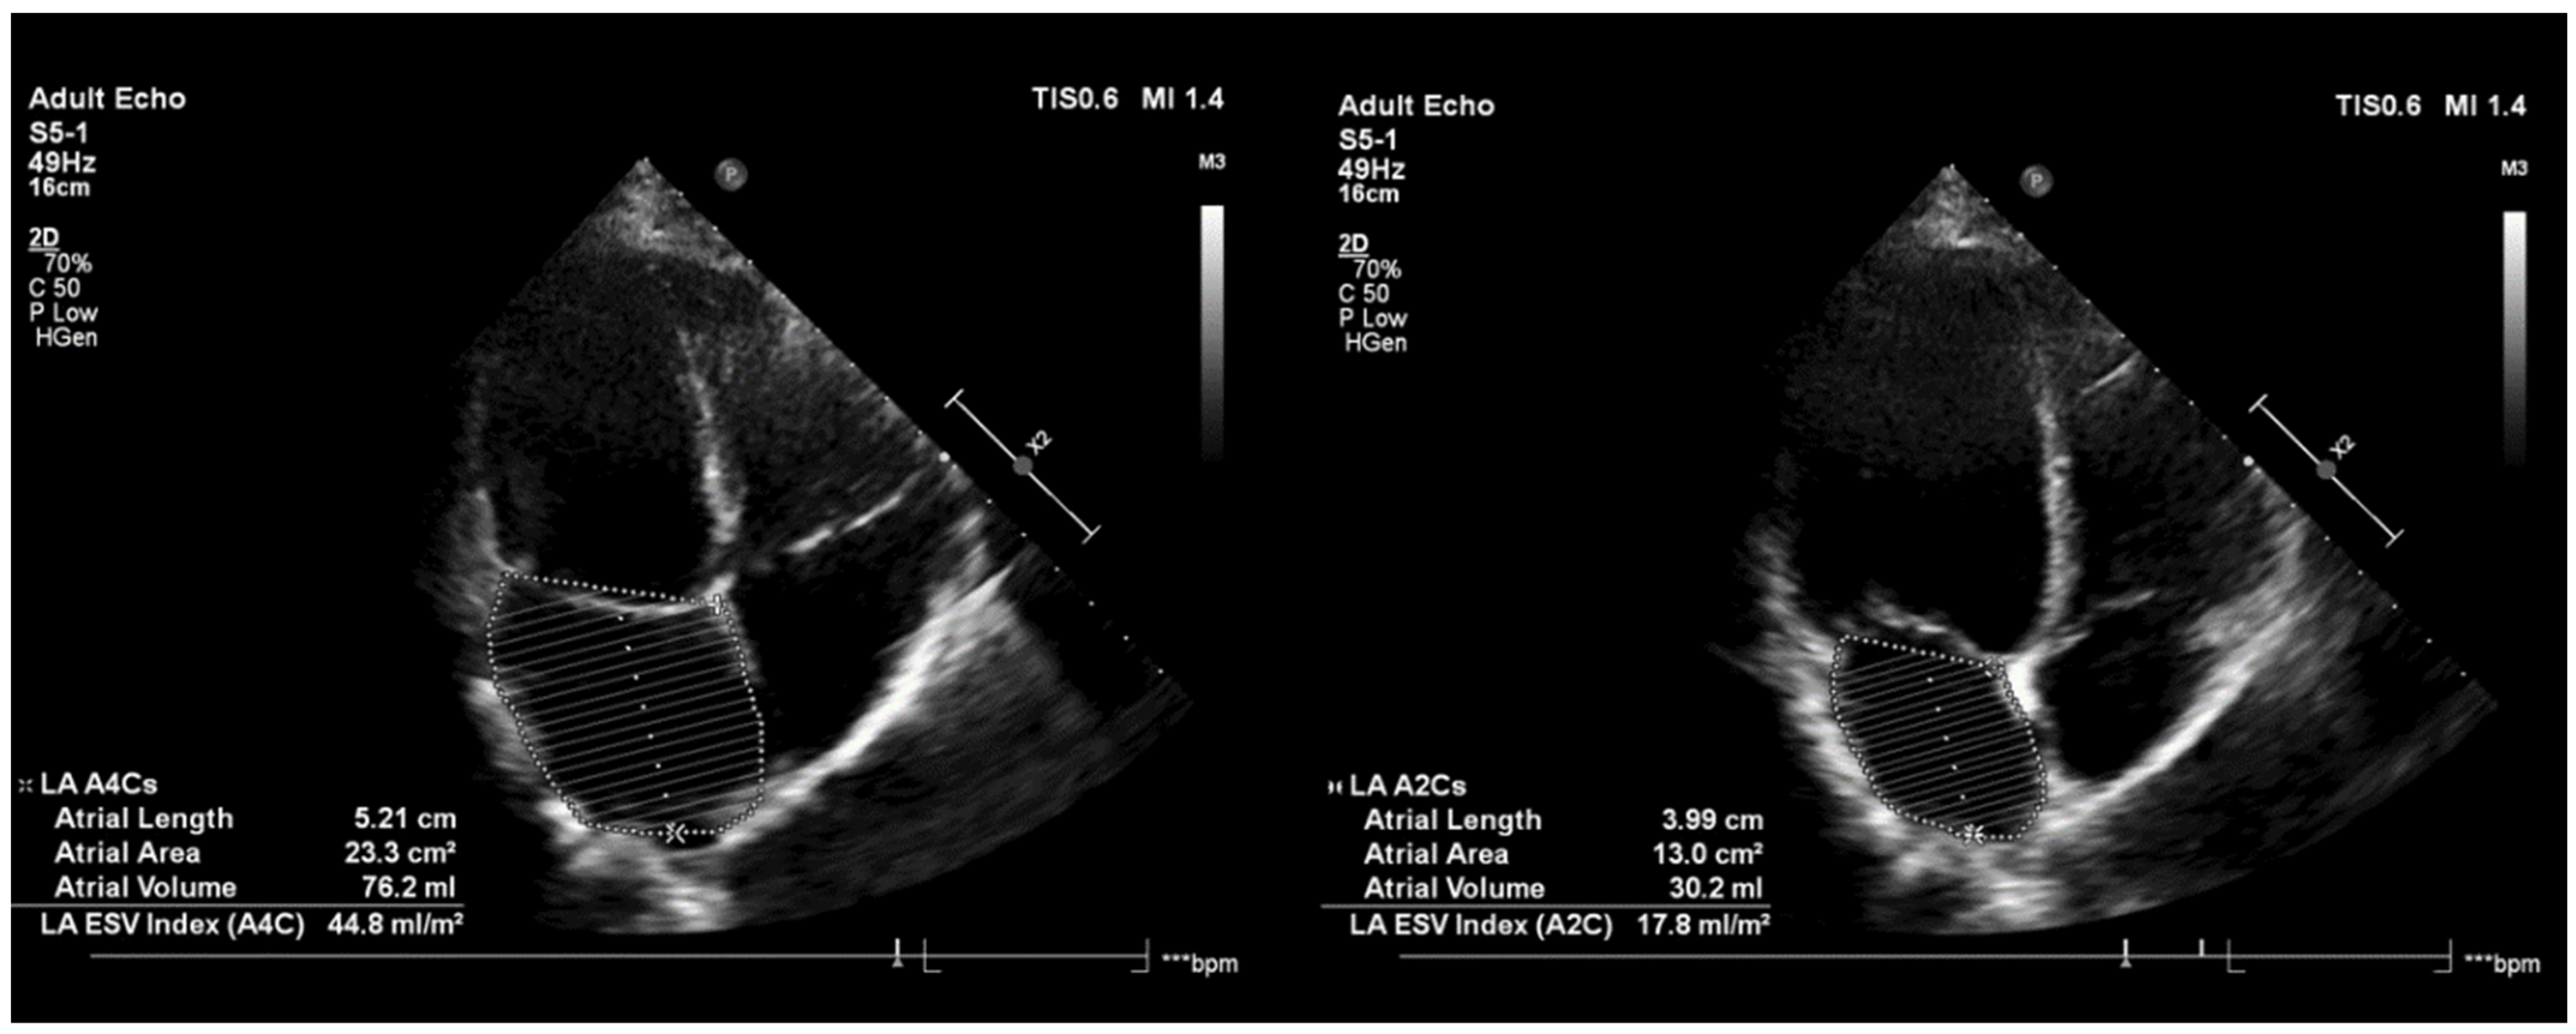

3.4. Post-Procedural LA Function by Echocardiography

4.3. LA Function Defined by Echocardiography Measurements

| Post-Procedural LA Function by Echocardiography | |||||||

|---|---|---|---|---|---|---|---|

| LA Parameters | HPSD RF (n = 21) | CB2 (n = 19) | Difference at 3-Month FU | ||||

| Pre-PVI | 3-Month FU | p Value | Pre-PVI | 3-Month FU | p Value | p Value | |

| LA size long (mm) | 56.8 ± 6.6 | 53.9 ± 5.0 | 0.325 | 58.1 ± 5.2 | 55.8 ± 5.3 | 0.148 | 0.572 |

| LA max area (cm2) | 22.6 ± 4.1 | 22.2 ± 3.6 | 0.778 | 23.4 ± 3.6 | 24.3 ± 4.1 | 0.307 | 0.235 |

| LA min area (cm2) | 14.9 ± 3.7 | 14.8 ± 3.6 | 0.845 | 14.7 ± 3.8 | 15.9 ± 4.6 | 0.211 | 0.633 |

| FAC | 33.7 ± 13.3 | 33.5 ± 10.8 | 0.808 | 38.1 ± 8.7 | 35.3 ± 12.3 | 0.525 | 0.319 |

| Peak E/A | 1.7 ± 2.6 | 1.2 ± 0.4 | 0.038 | 1.3 ± 0.4 | 1.1 ± 0.2 | 0.855 | 0.287 |

| LA EDV (ml) | 77.3 ± 34.8 | 67.6 ± 18.4 | 0.196 | 69.2 ± 20.1 | 74.0 ± 19.9 | 0.164 | 0.408 |

| LA ESV (ml) | 35.8 ± 13.5 | 34.9 ± 14.8 | 0102 | 34.2 ± 13.6 | 37.5 ± 17.0 | 0.348 | 0.129 |

| LA EF (%) | 50.2 ± 19.7 | 49.6 ± 14.8 | 0.903 | 49.7 ± 15.5 | 50.8 ± 13.4 | 0.847 | 0.671 |

| E | 64.7 ± 15.6 | 67.1 ± 20.7 | 0.382 | 72.8 ± 18.1 | 68.5 ± 16.7 | 0.599 | 0.238 |

| E’ | 10.4 ± 2.5 | 10.0 ± 3.5 | 0.395 | 12.5 ± 3.5 | 10.9 ± 3.1 | 0.105 | 0.568 |

| E/E’ | 6.6 ± 2.6 | 7.32 ± 3.1 | 0.326 | 6.2 ± 1.9 | 6.6 ± 1.9 | 0.121 | 0.972 |